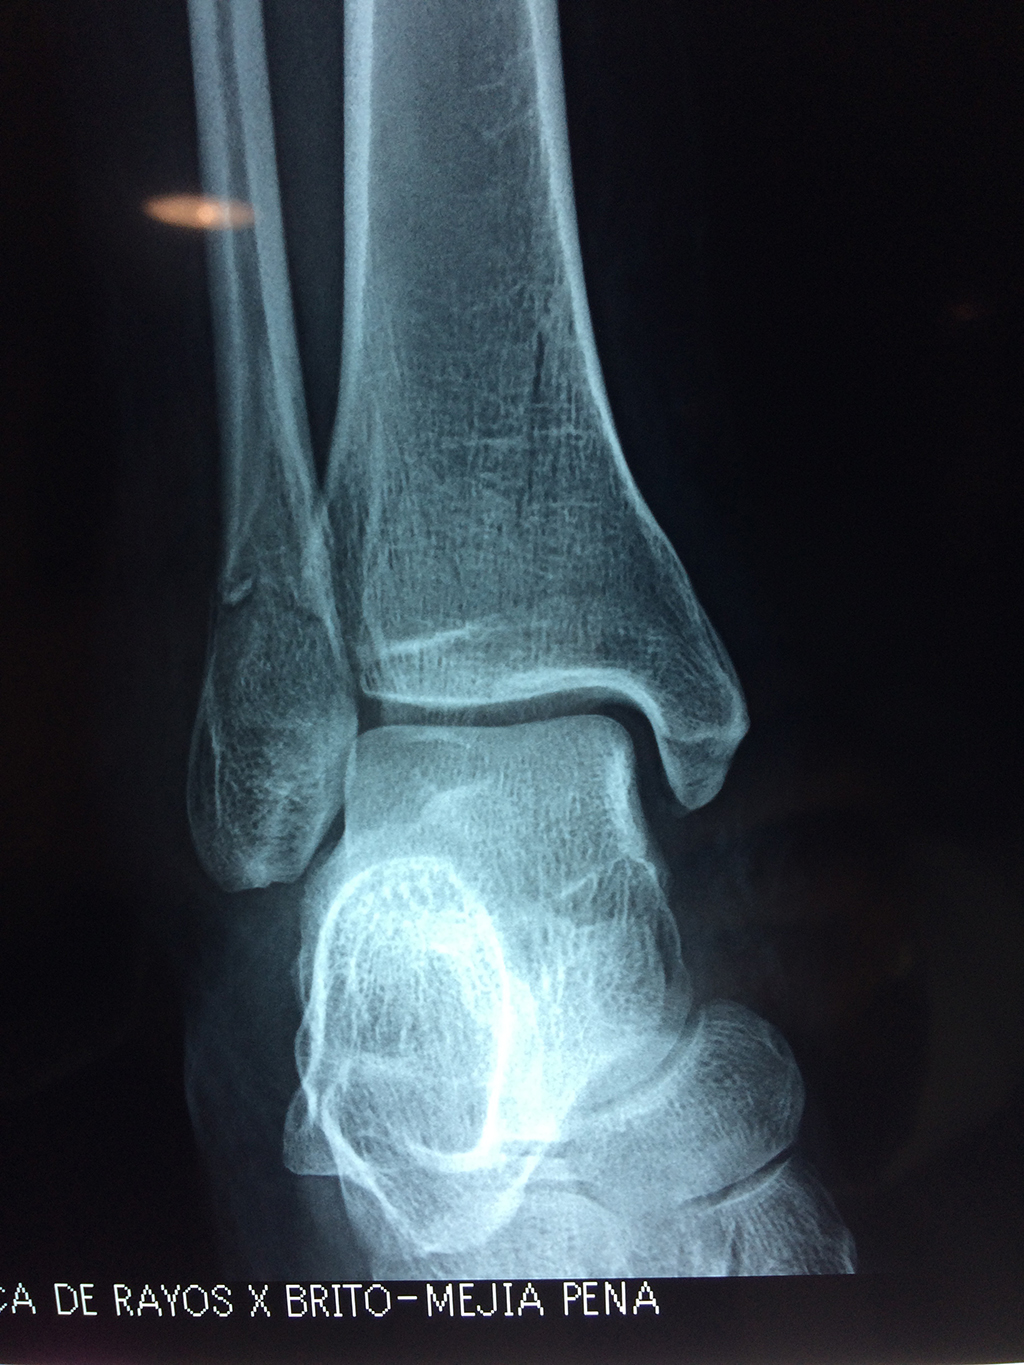

Una fractura de tobillo es la rotura de uno o más de los huesos del tobillo. Estas fracturas pueden ser:

• Parciales (el hueso está sólo parcialmente fisurado, no del todo).

• Completas (el hueso está perforado y está en 2 partes).

• Producirse en uno o ambos lados del tobillo.

Algunas fracturas de tobillo pueden requerir cirugía si:

• Los extremos de los huesos están desalineados entre sí (desplazados).

• La fractura se extiende hasta la articulación del tobillo (fractura intra-articular).

• Los tendones o ligamentos (tejidos que sujetan los músculos y los huesos entre sí) están rotos.

• El médico cree que sus huesos probablemente no sanen apropiadamente sin cirugía.

• El médico considera que la cirugía puede permitirle una recuperación más rápida y confiable.

• En los niños, la fractura involucra la parte del hueso del tobillo donde el hueso está creciendo.

Cuando se necesita cirugía, es probable que esta implique el uso de clavijas de metal, tornillos o placas para sostener los huesos en su lugar mientras la fractura se consolida. Los elementos de soporte pueden ser temporales o permanentes.